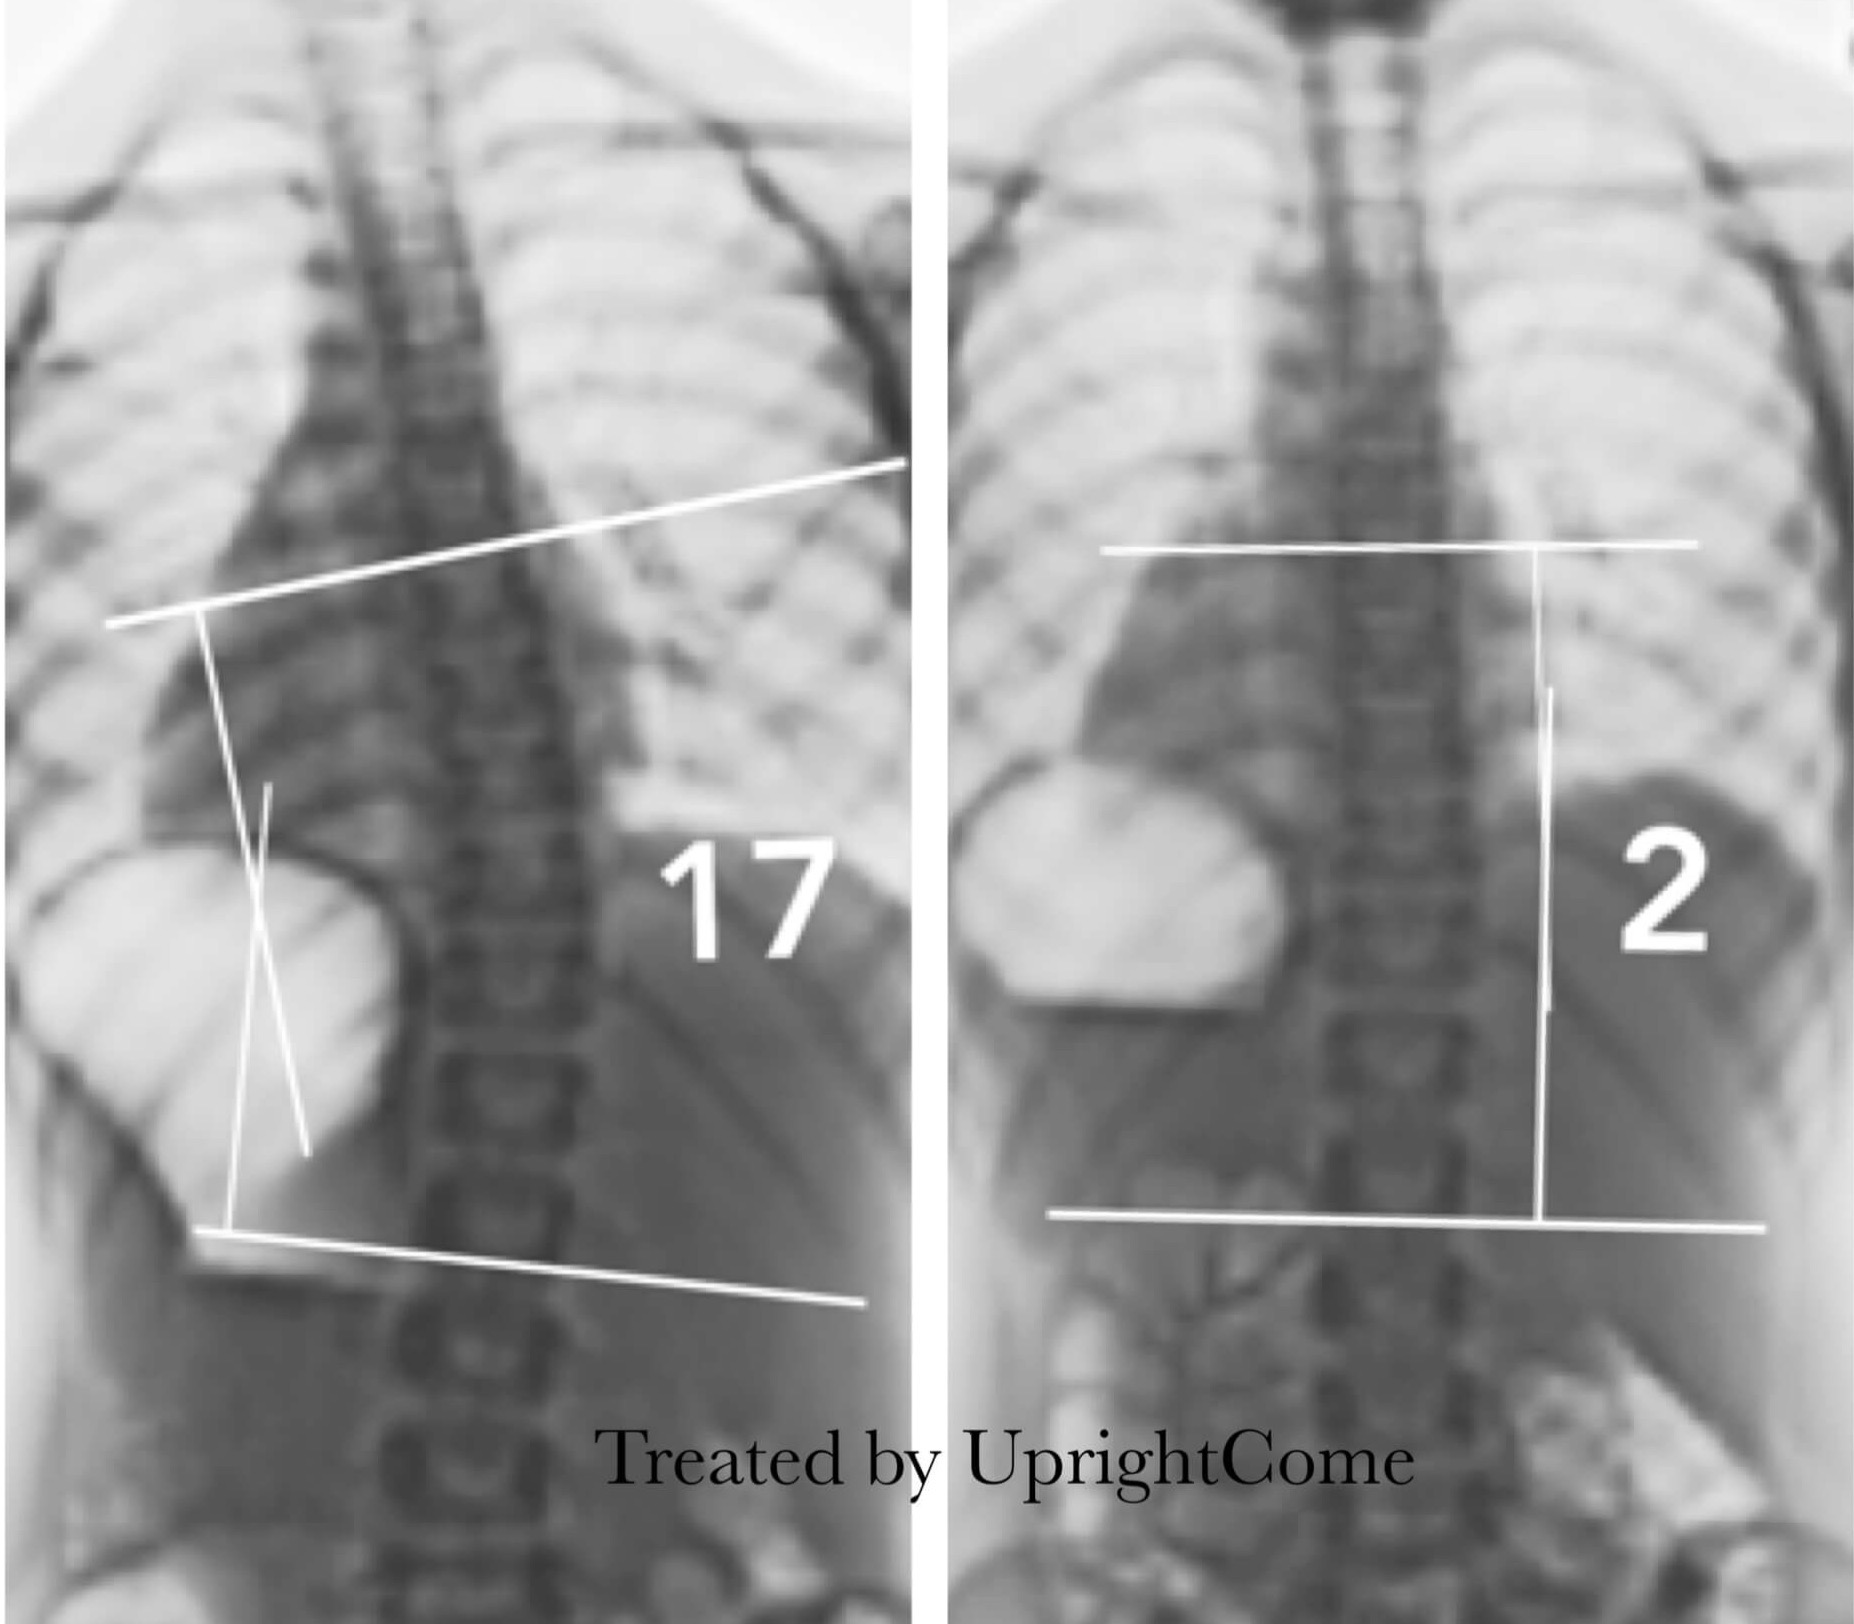

Case 7, 11 years old, 17° Cobb

![脊椎側彎患者經過側彎矯正治療後,腰椎角度由17度減少到2度。]()